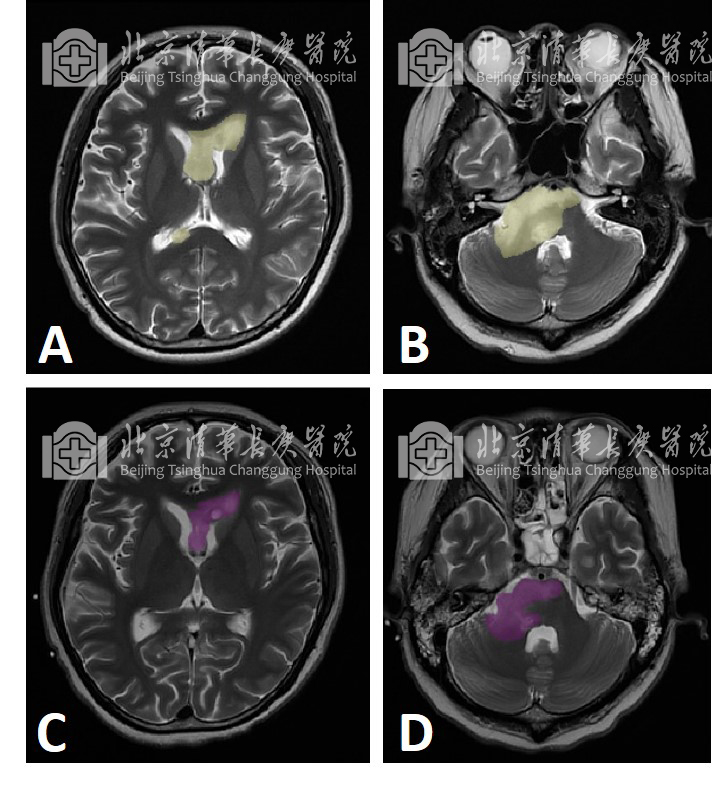

图1:男性,25岁,系颈髓原发DMG伴有H3K27M突变肿瘤患者,在颈髓肿瘤近全切除术后出现大面积颅内转移,由于肿瘤呈弥漫性生长,广泛侵犯脑干、胼胝体等中线核心结构,手术无法切除,经清华长庚弥漫中线MDT团队联合诊疗后,头颅MRI扫描结果对比可见肿瘤体积显著缩小(T2加权像轴位,A.B为综合靶向治疗前,肿瘤以黄色标识;C.D 为综合靶向治疗后,肿瘤以紫色标识),该患者至今已生存3.5年,治疗和随访工作仍在持续进行中。